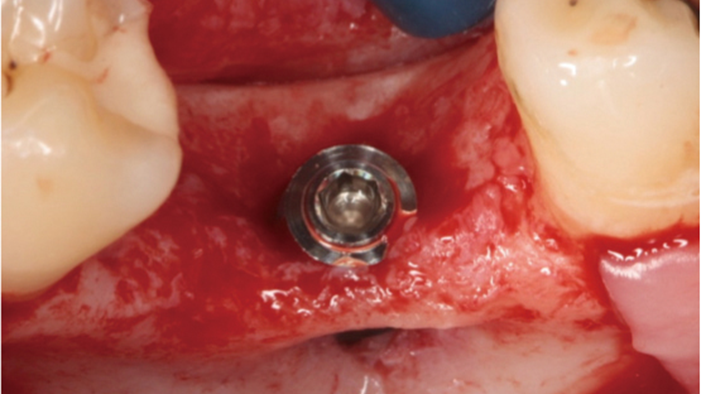

Clinical case: # 46 implant placement & GBR using i-Gen membrane for significant vertical resorption & mixed bone defect

- Courtesy of Dr. Iulian Filipov, Romania -

AnyRidge, mandibular posterior, i-Gen, resorption, bone defect, bone regeneration, space management, #46, GBR, Dr. Iulian Filipov

AnyRidge implant system, i-Gen